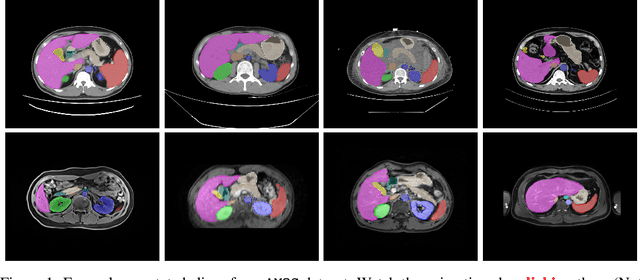

Abstract:Despite the considerable progress in automatic abdominal multi-organ segmentation from CT/MRI scans in recent years, a comprehensive evaluation of the models' capabilities is hampered by the lack of a large-scale benchmark from diverse clinical scenarios. Constraint by the high cost of collecting and labeling 3D medical data, most of the deep learning models to date are driven by datasets with a limited number of organs of interest or samples, which still limits the power of modern deep models and makes it difficult to provide a fully comprehensive and fair estimate of various methods. To mitigate the limitations, we present AMOS, a large-scale, diverse, clinical dataset for abdominal organ segmentation. AMOS provides 500 CT and 100 MRI scans collected from multi-center, multi-vendor, multi-modality, multi-phase, multi-disease patients, each with voxel-level annotations of 15 abdominal organs, providing challenging examples and test-bed for studying robust segmentation algorithms under diverse targets and scenarios. We further benchmark several state-of-the-art medical segmentation models to evaluate the status of the existing methods on this new challenging dataset. We have made our datasets, benchmark servers, and baselines publicly available, and hope to inspire future research. Information can be found at https://amos22.grand-challenge.org.